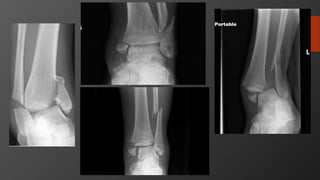

Tibial Plateau Factures

Tibial Plateau Fracture

• Mechanism

• Varus/valgus load with or without axial load

• Like fall from height

• Imaging:

• X-Ray: AP, Lateral

• CT for preop planning, assessing articular depression

• MRI

• ABI if any differences in pulses between limbs